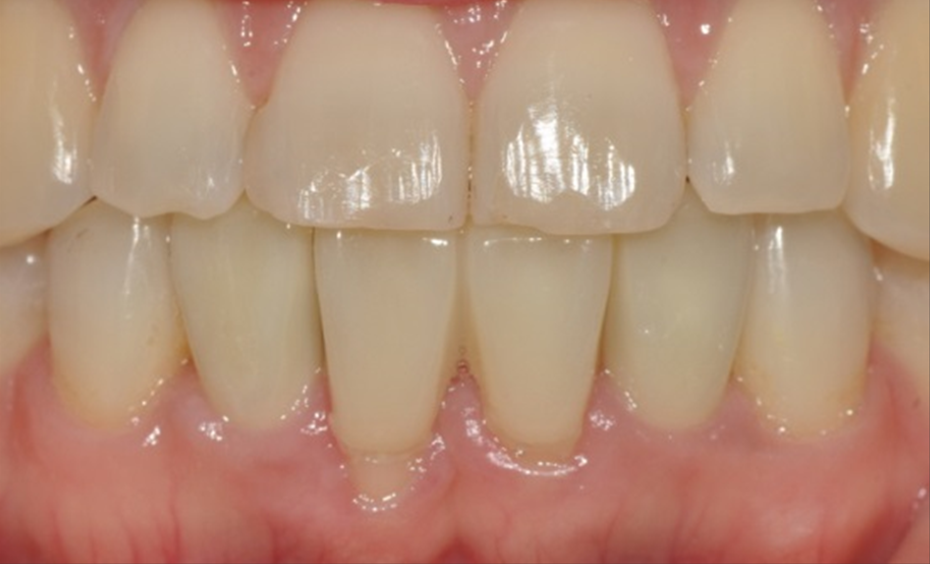

마지막으로 Short Abutment를 사용하여 zirconia cement retained type 최종 보철물을 완성하였다 [그림 11, 12].

최종 보철물 제작 2개월 후 구강 내 사진에서 만족스러운 연조직 치유 양상을 확인할 수 있다 [그림 13].